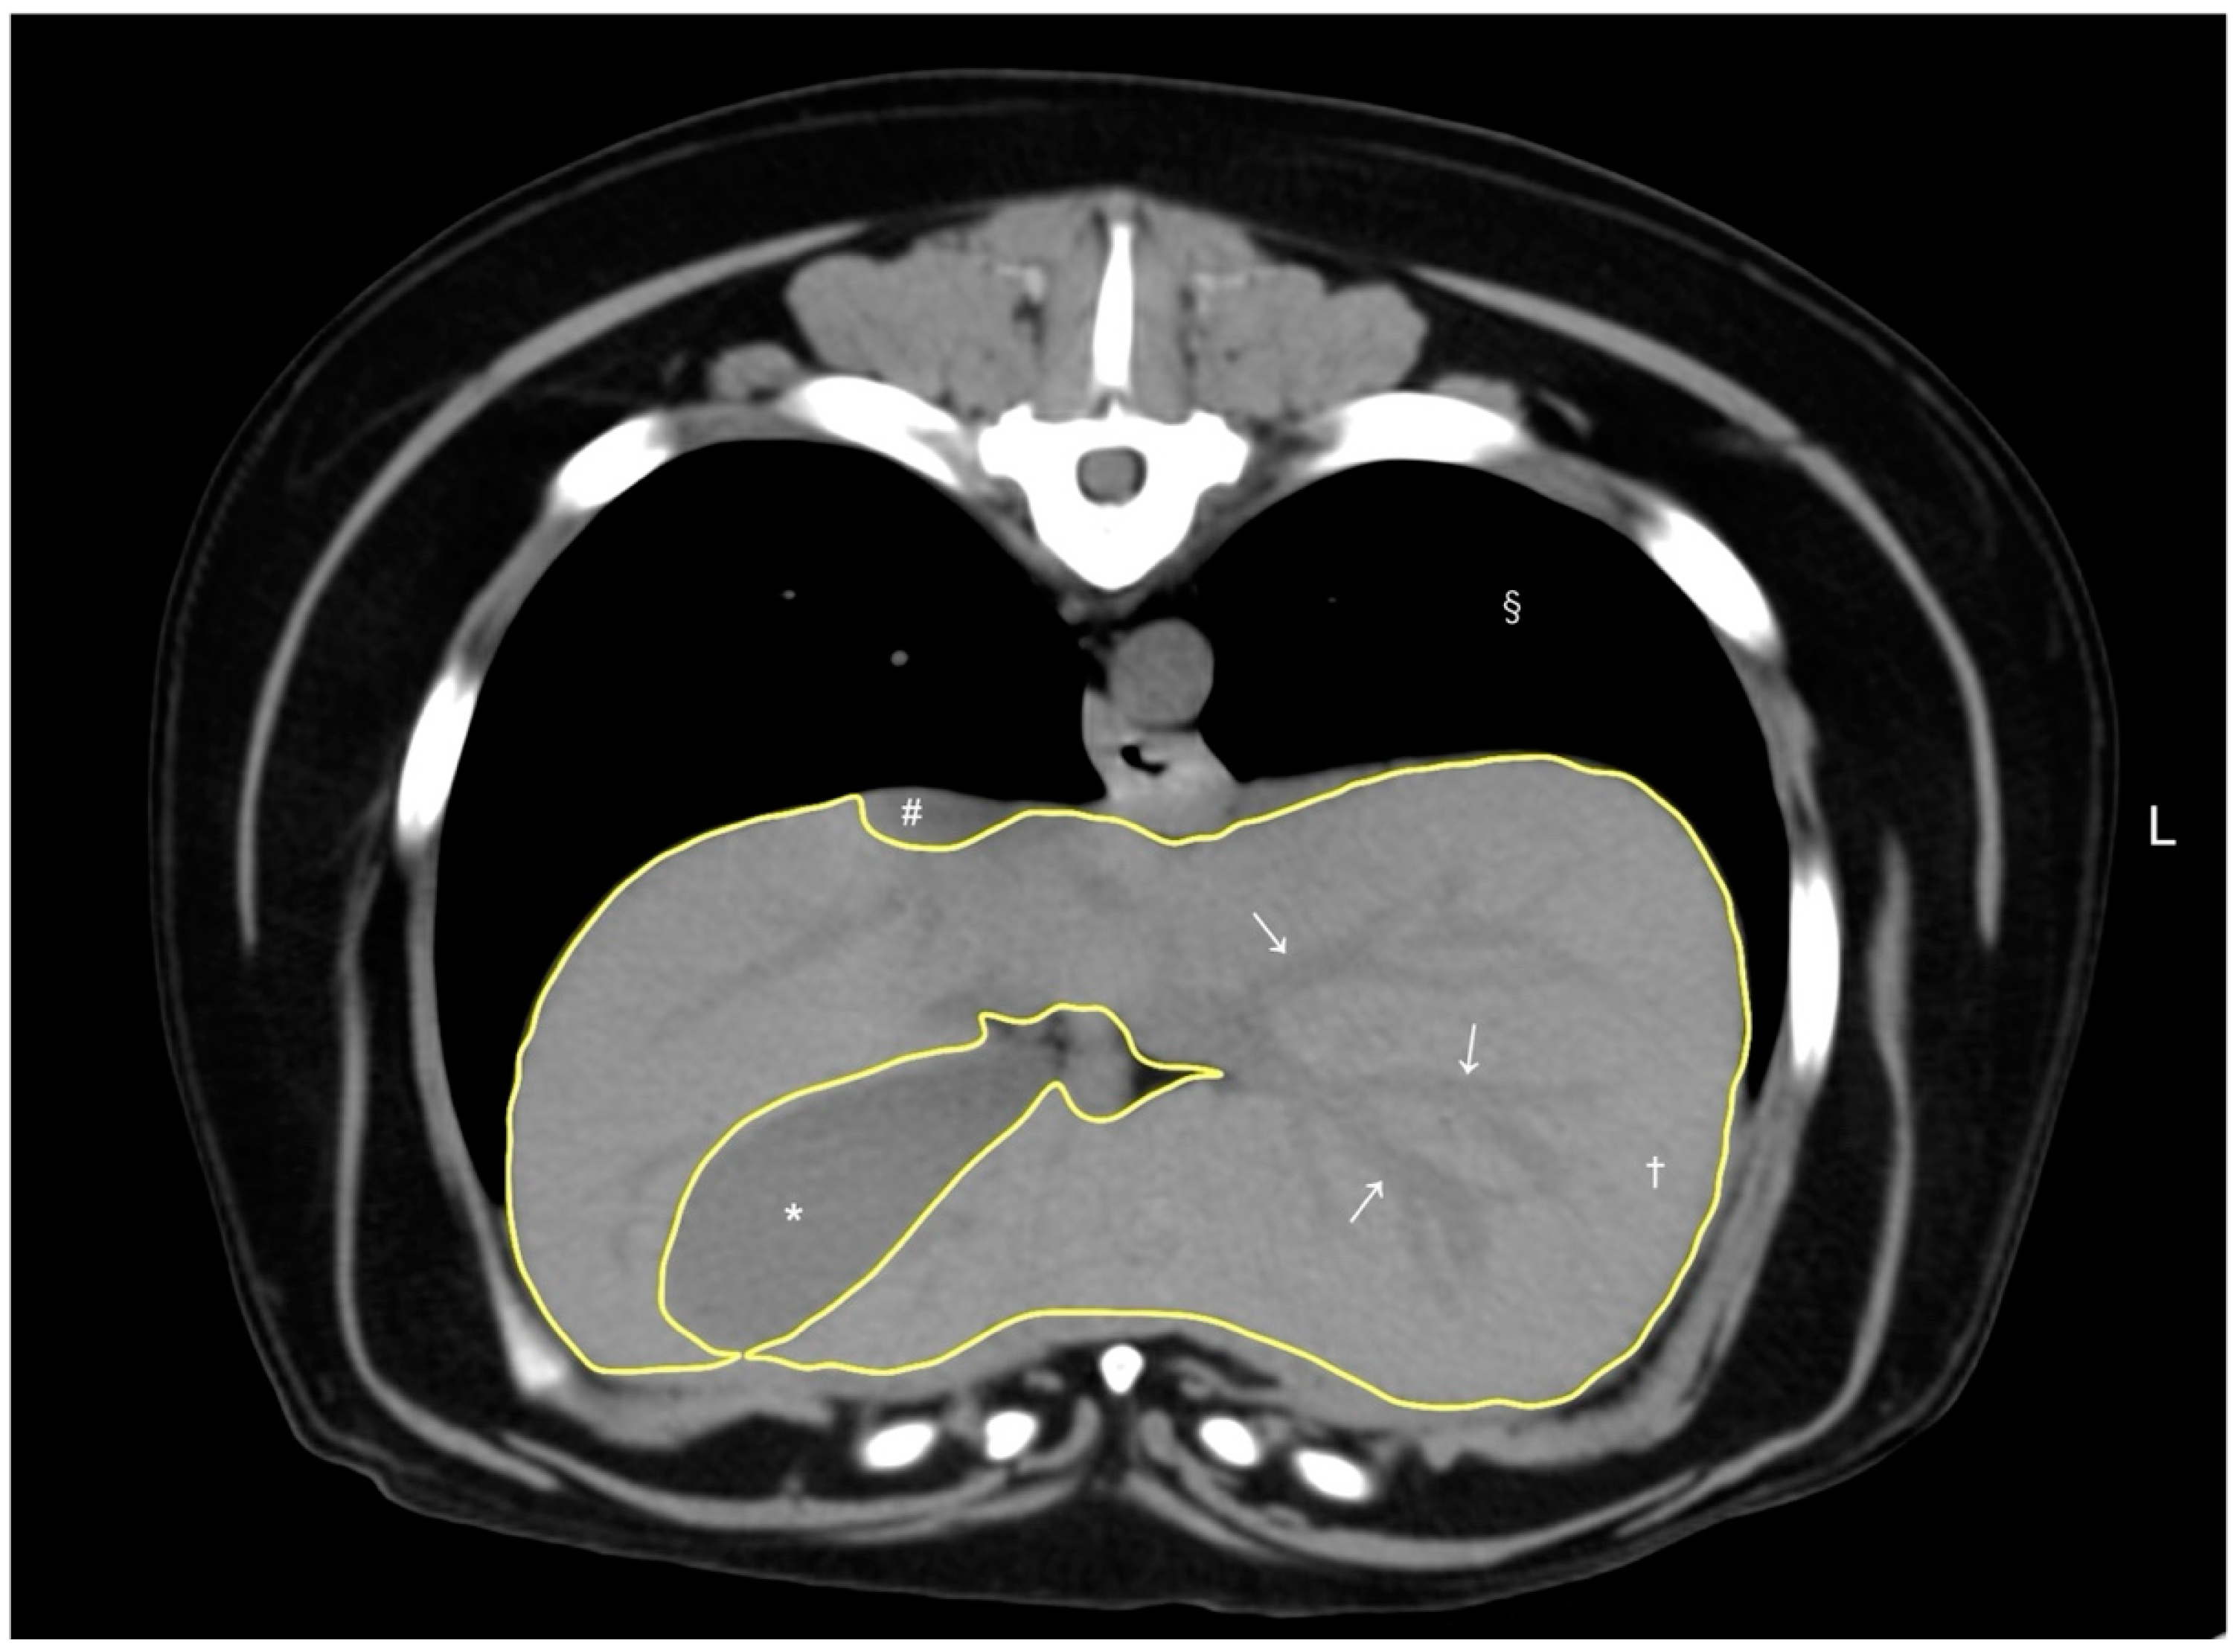

A volumetry of the livers was conducted using CT by a veterinarian (RN) trained under the supervision of the radiologist (MM), using a DICOM viewer (Horos, version 4.0.0., https://horosproject.org [accessed on 12 January 2020]) in accordance with methodologies established in previous studies [8,9]. For all dogs, the window width and window level were adjusted to 350–400 HU and 40 HU, respectively. For liver segmentation, the entire liver was manually delineated into an operator-defined region of interest (ROI) in the transverse plane of the pre-contrast image, extending from the cranial border at the diaphragm to the caudal borders adjacent to the right kidney and spleen. Hepatic vessels within the hepatic parenchyma were included in the ROIs, while visible hepatic lobe fissures, the gallbladder, and hepatic vessels outside the hepatic parenchymal boundary were excluded according to previous reports [8,9]. To enhance efficiency, liver margins were traced instead of filling in the liver parenchyma (Figure 1). After manually outlining the ROIs on more than 20 slices with equal interslice gaps, the liver volume derived by CT was obtained using the following formula: Σ {each slice area (cm2) × slice thickness (cm)} × total number of slices of hepatic parenchyma/number of slices used for calculation, following the protocols from previous reports [8]. Finally, the CT-based liver volume was divided by the dog’s body weight (kg) to determine the normalized CT-based liver volume for each case, as body weight has been reported to be the best normalization factor for liver volumetry [9].

Figure 1.

A representative image of abdominal CT transverse pre-contrast images using CT liver volumetry in dogs. The window width and window level were adjusted to 350–400 HU and 40 HU, respectively. The liver segmentation was manually traced as a region of interest (ROI, yellow line). Hepatic vessels (white arrows) within the hepatic parenchyma (†) were included in the ROI, whereas the gallbladder (*), visible liver lobe fissures, and hepatic vessels outside the hepatic parenchymal margin were excluded. The caudal vena cava (#) and pulmonary parenchyma (§) were also noted.